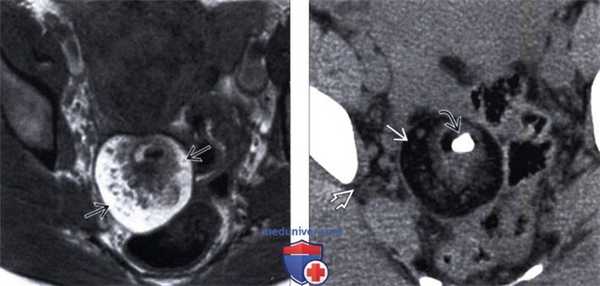

(Слева) На МРТ Т1 дермоид имеет гиперинтенсивный внутренний сигнал, который представляет собой скопление жира.

(Справа) КТ с контрастированием того же дермоида, аксиальный срез: определяется кальцинированный зуб, который обнаруживается в 1/3 случаев. Обратите внимание, что жир в дермоиде заметно гиподенсивнее по сравнению с внебрюшинным жиром.